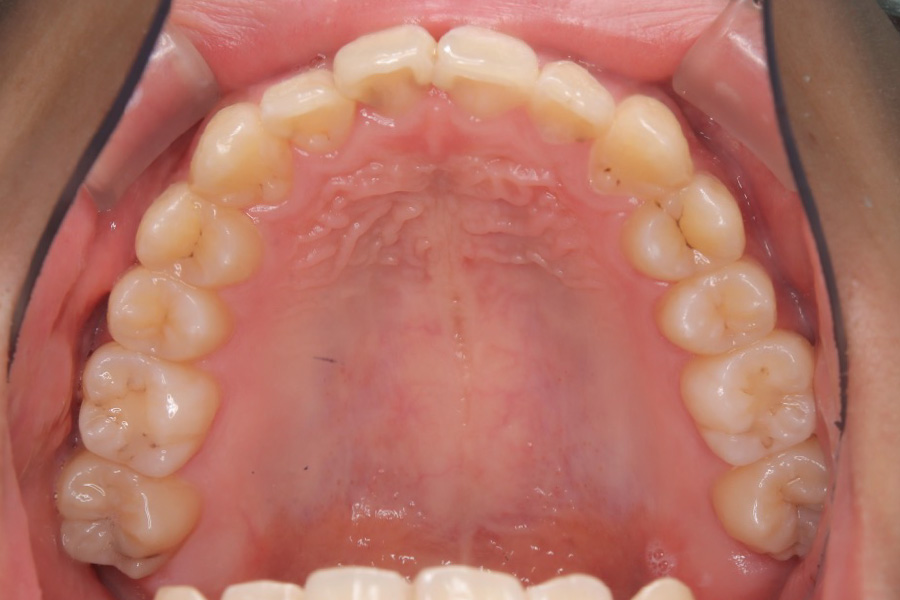

治療後

治療内容 インビザライン矯正

非抜歯

治療に伴うリスク 矯正終了後は、リテーナーを指示通りに使用し、歯の後戻りを防ぐ必要があります。